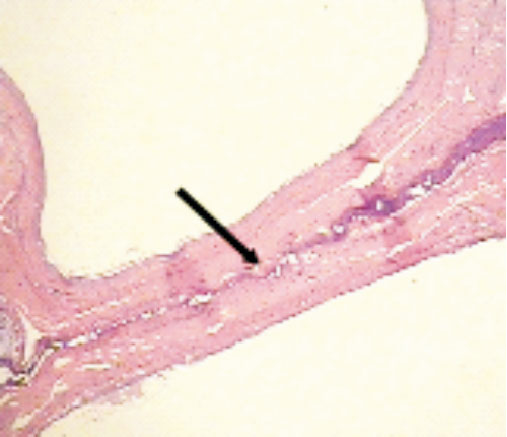

光學顯微鏡下,高頻焊接儀閉合腸管的主要病理改變為急性熱損傷及壓力損傷,表現為組織細胞蛋白變性、凝固性壞死及玻璃樣變,組織結構被破壞,細胞界限不清,細胞核固縮、溶解或消失(如圖 3箭頭所示),焊接處兩側腸黏膜粘合緊密(如圖 4箭頭所示)。